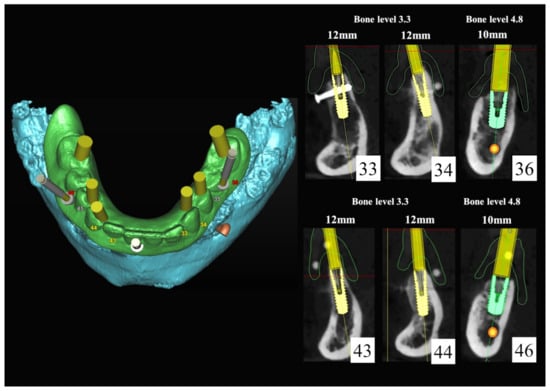

The number, the length, the diameter and the placement of computational virtual implants were determined with respect to the design of the final prosthesis the available residual bone volume and the anatomical limitations according to the previously described technical procedure (Figure 16, Figure 17, Figure 18, Figure 19, Figure 20 and Figure 21).

Figure 16.

Three-dimensional (3D) CBCT scan images with the patient wearing the planned prosthesis.

Figure 17.

Three-dimensional (3D) CBCT scan images of the prosthesis equipped with integrated radiopaque reference spheres scanned separately.

Figure 18.

Three-dimensional (3D) planning of the number, the diameter and the axis of dental implants with respect to the design of the final virtual maxillary prosthesis.

Figure 19.

Figure 20.

Maxillary and mandibular virtual surgical drilling guides designed according to the implant position.

Figure 21.

Final maxillary and mandibular stereolithographic surgical drilling guides.

6.2.4. Intra-Operative Documentation:

In March 2013, twelve guided dental implants were placed at sites # 12, # 13, # 15, # 22, # 23, # 25, # 33, # 34, # 36, # 43, # 44, and # 46 (Figure 22, Figure 23, Figure 24, Figure 25 and Figure 26)